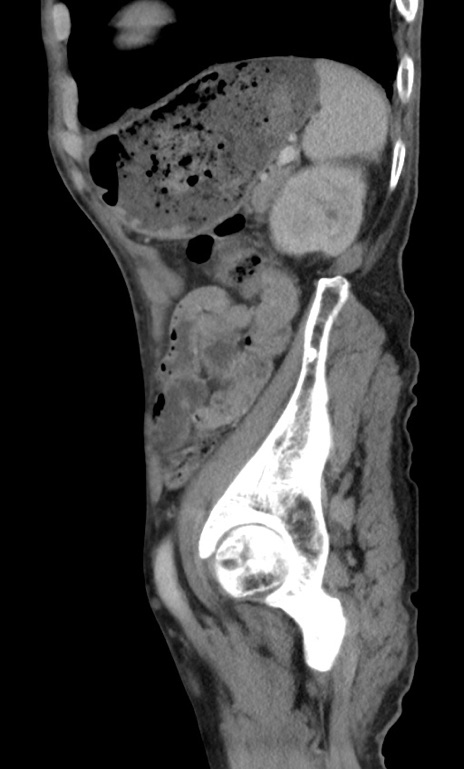

症例3(矢状断像)

【症例】 70歳代男性

【主訴】右鼠径部腫瘤、疼痛

【現病歴】本日朝より上記主訴あり、受診。

【既往歴】膀胱癌にて膀胱全摘、両側尿管皮膚瘻

【データ】WBC 5600、CRP 0.56